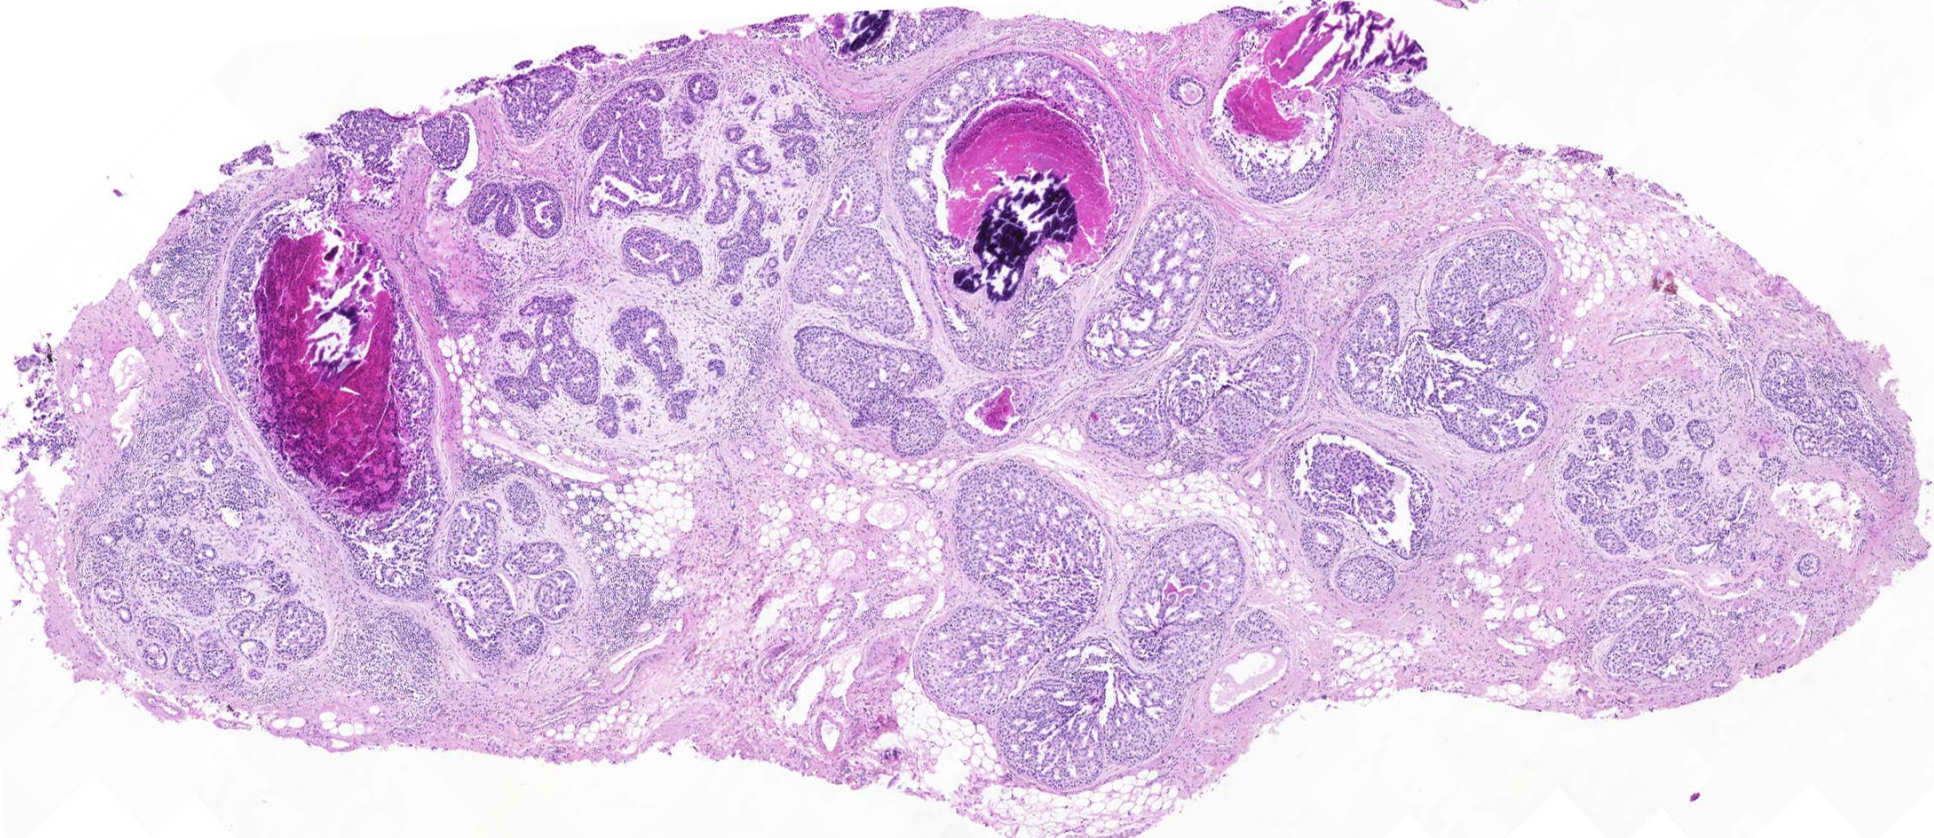

We are currently focused on two main areas of research: firstly, the analysis of DNA mutations in the normal and malignant breast and colon tissue; and secondly, the use of cancer-associated miRNA as potential biomarkers and therapeutic targets.

- Analysis of markers of proliferation and apoptosis in normal breast and breast cancer tissue from different time points in the reproductive age, recording age of pregnancy and of cancer onset

- Investigation of genetics and epigenetics changes of the normal and malignant breast and colon by detecting single nucleotide variants, insertions/deletions, copy number changes, and large structural variants